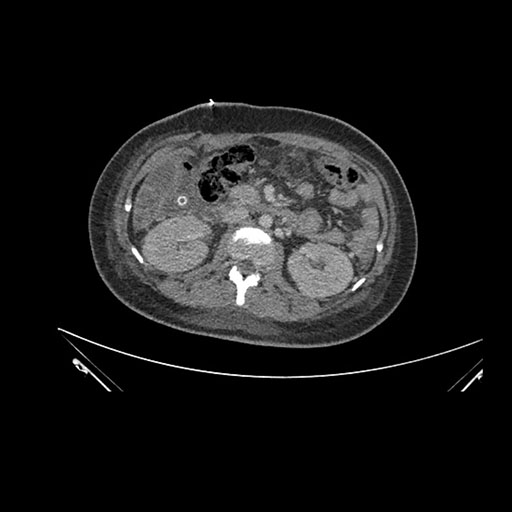

Imaging Analysis

Look through the patient's CT scan to identify any areas of concern for the necessary procedure.

Axial Arterial

Based on initial findings, which issue(s) would you be most concerned about?